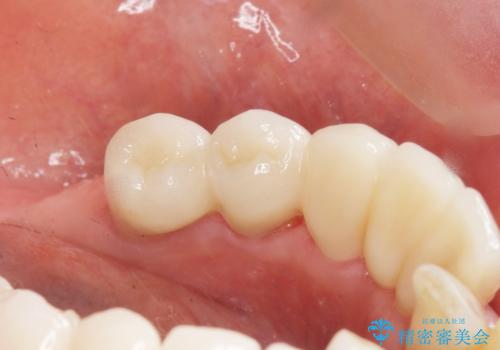

入れ歯も抵抗があるとのことから、相談を重ね、今の状態では保存不可能な下の前歯(左下2)を抜去し、ブリッジや連結補綴により動揺を抑えることにしました。

気にされていた前歯と奥歯の動揺がなくなったことと自然な仕上がりに喜んで頂けました。

クラウンの種類:オールセラミッククラウン スタンダード